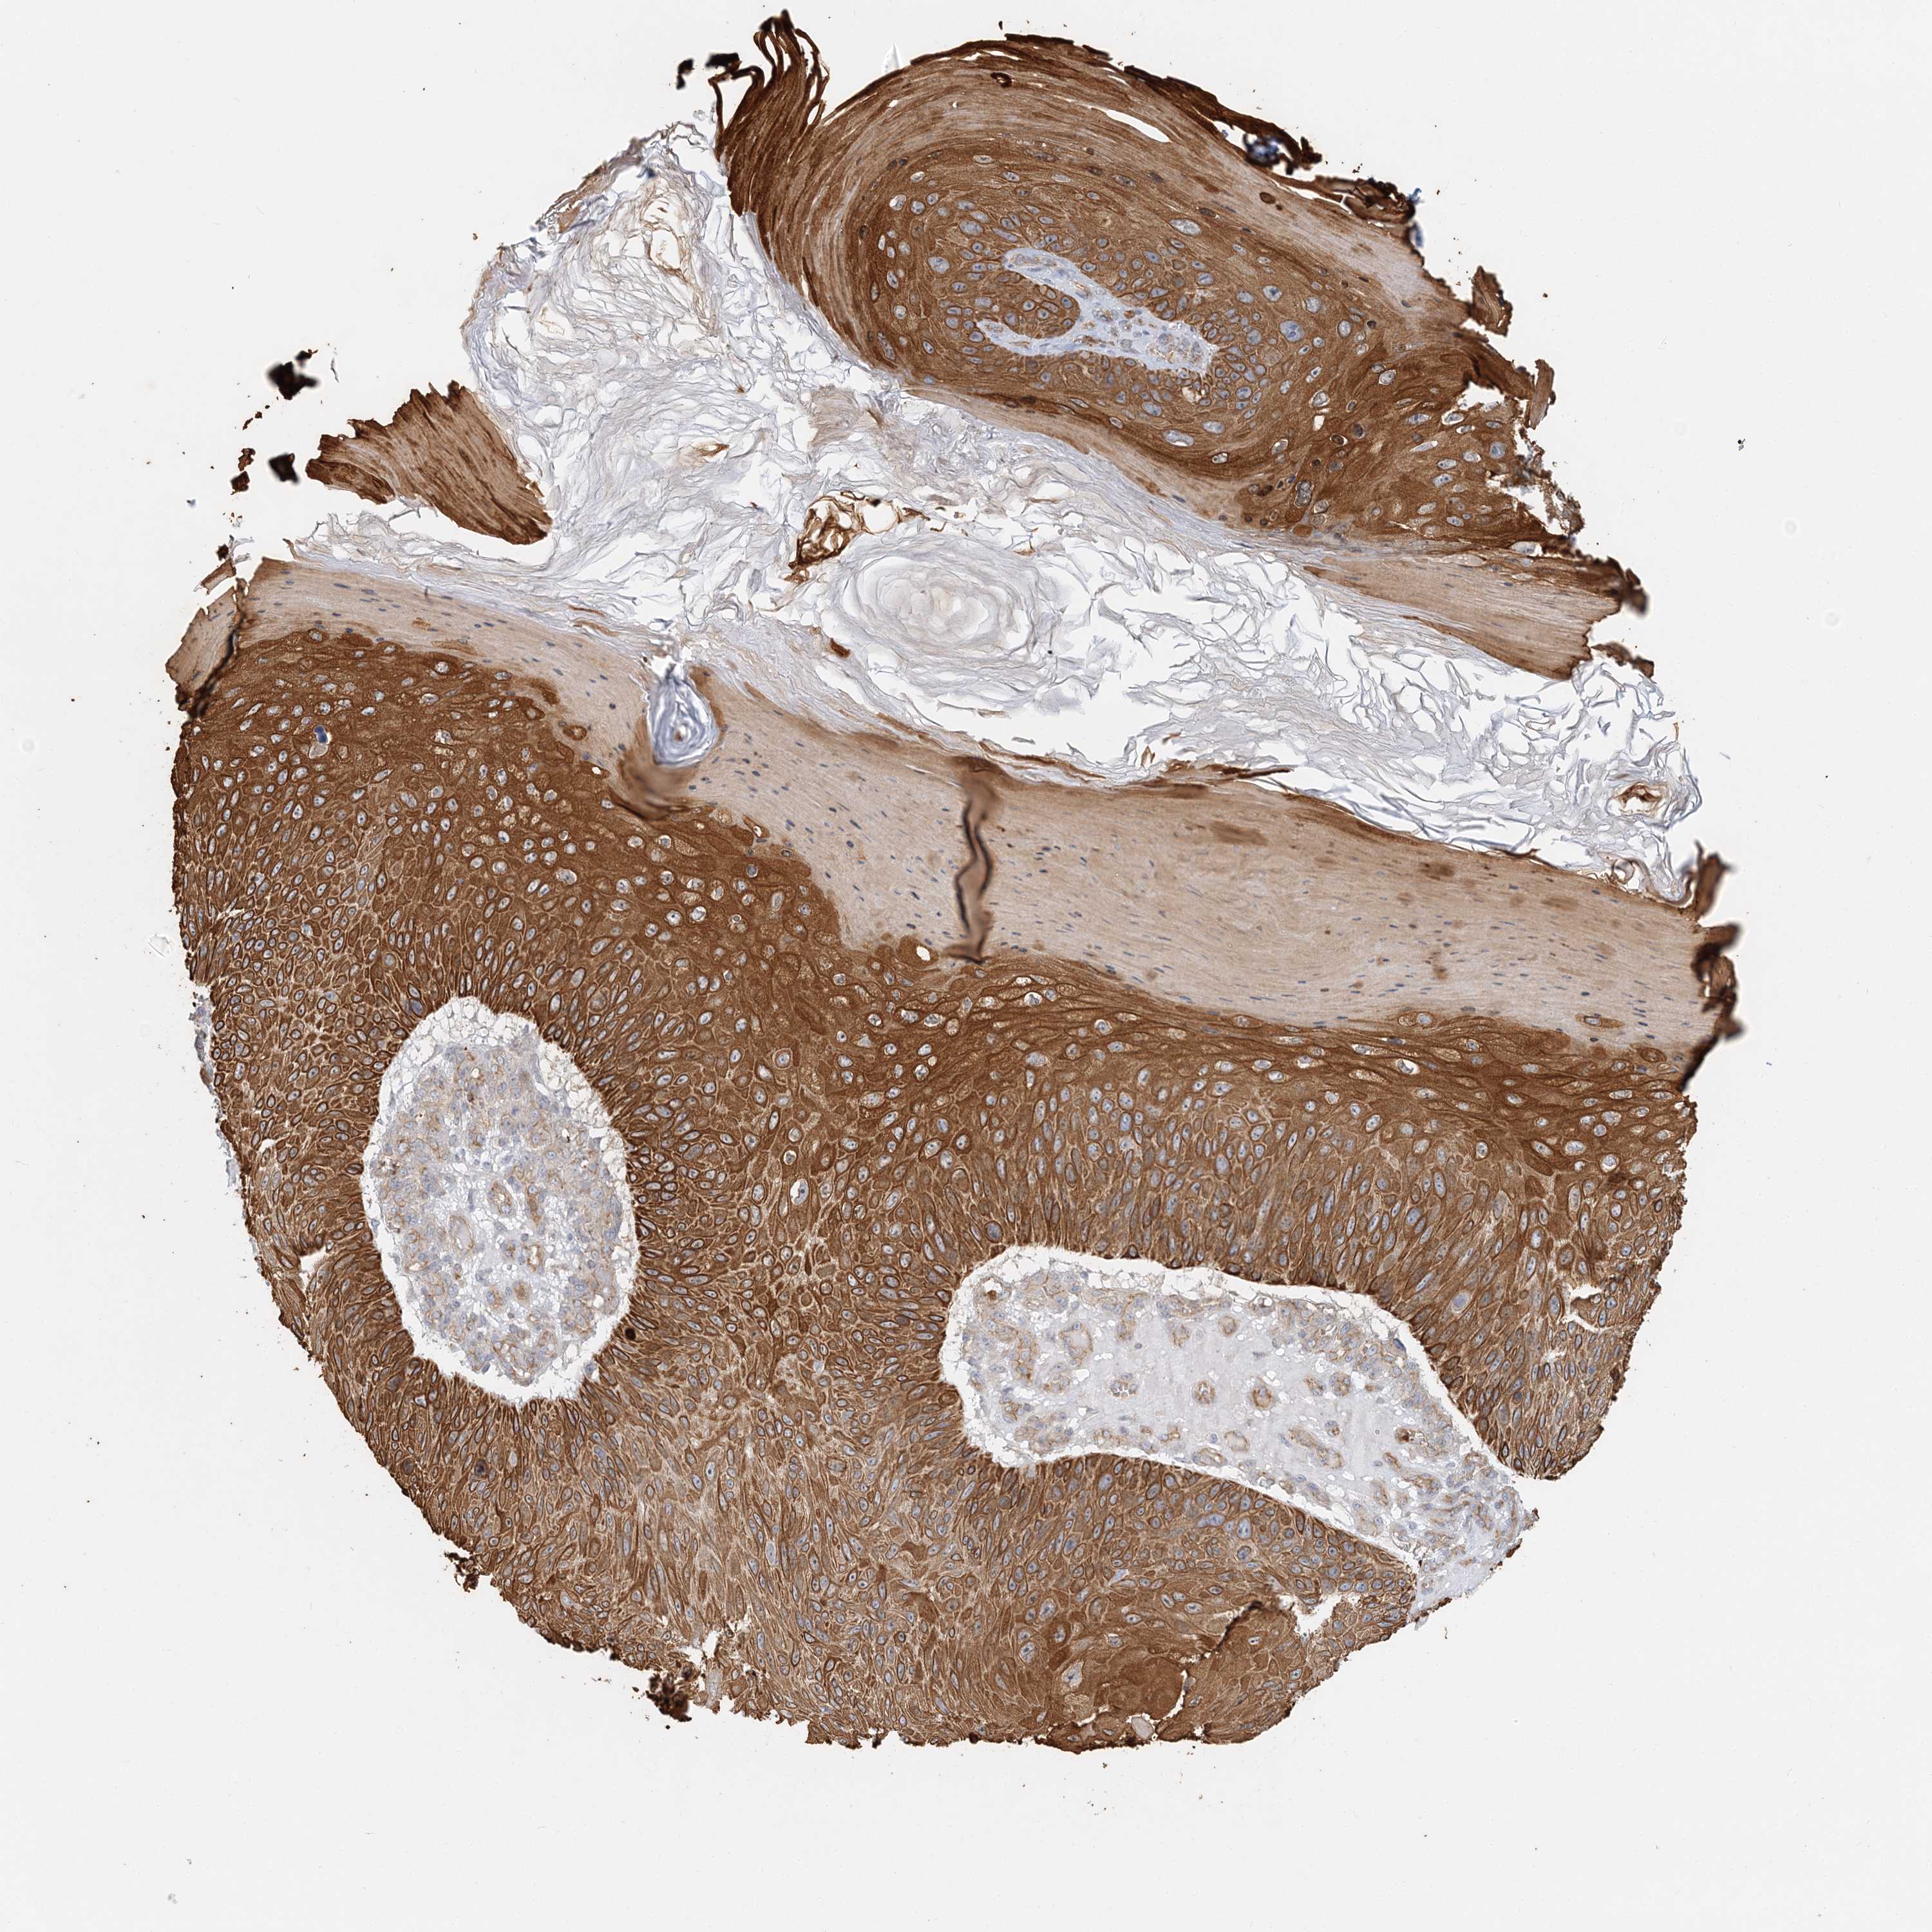

SKIN CANCER - Protein expressioni

A mouse-over function shows sample information and annotation data. Click on an image to view it in a full screen mode. Samples can be filtered based on level of antibody staining by selecting one or several of the following categories: high, medium, low and not detected. The assay and annotation is described here.

Each image is clickable and will lead to virtual microscopy that enables deeper exploration of all samples and also displays staining intensity scores, fraction scores and subcellular localization as well as patient and tissue information for each sample.

Antibody HPA036806

Squamous cell carcinoma, metastatic, NOS